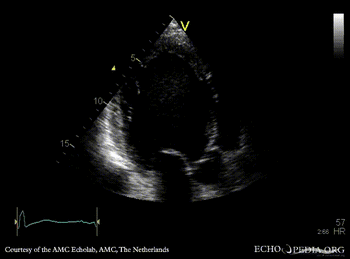

| PLAX: Dilated left ventricle with poor function | A4CH |

| A2CH | A3CH |